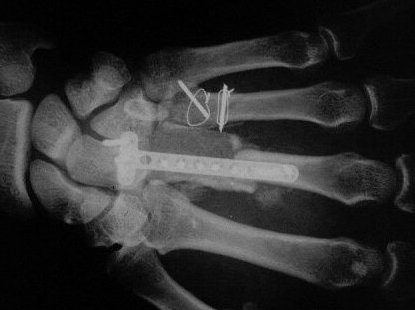

Primary bone graft with carpometacarpal arthrodesis. Quantitative cultures from the end of the case were negative.